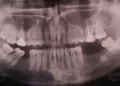

Мне 18 лет. Сначала болел зуб, далее образовалась шишка. Я не могла есть на одной стороне. Десна в нижней части в самом конце начала отрываться, болело. Далее перестало. Сейчас в десне маленькая дырочка, там торчит белая маленькая штука, жесткая и похожая на зуб. У меня всего 29 зубов.

Возможно ли что это растёт зуб мудрости или это что-то другое?

Да, вполне возможно, это прорезывается 8-й зуб.

Для облегчения его прорезывания можно обратиться к стоматологу-хирургу для рассечения десны, таким образом, зуб прорежется быстрее и без осложнений.